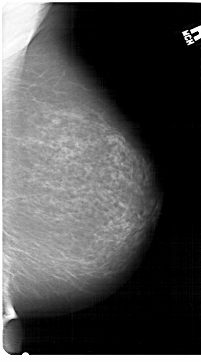

A_1307_1.LEFT_CC

LEFT_CC LINES 6871 PIXELS_PER_LINE 4006 BITS_PER_PIXEL 12 RESOLUTION 43.5 OVERLAY